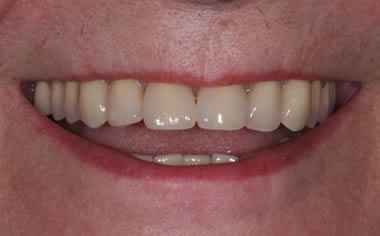

Full arches of teeth replaced by dental implants

Case Two (8 images)

Full set of lower teeth fixed onto five dental implants.